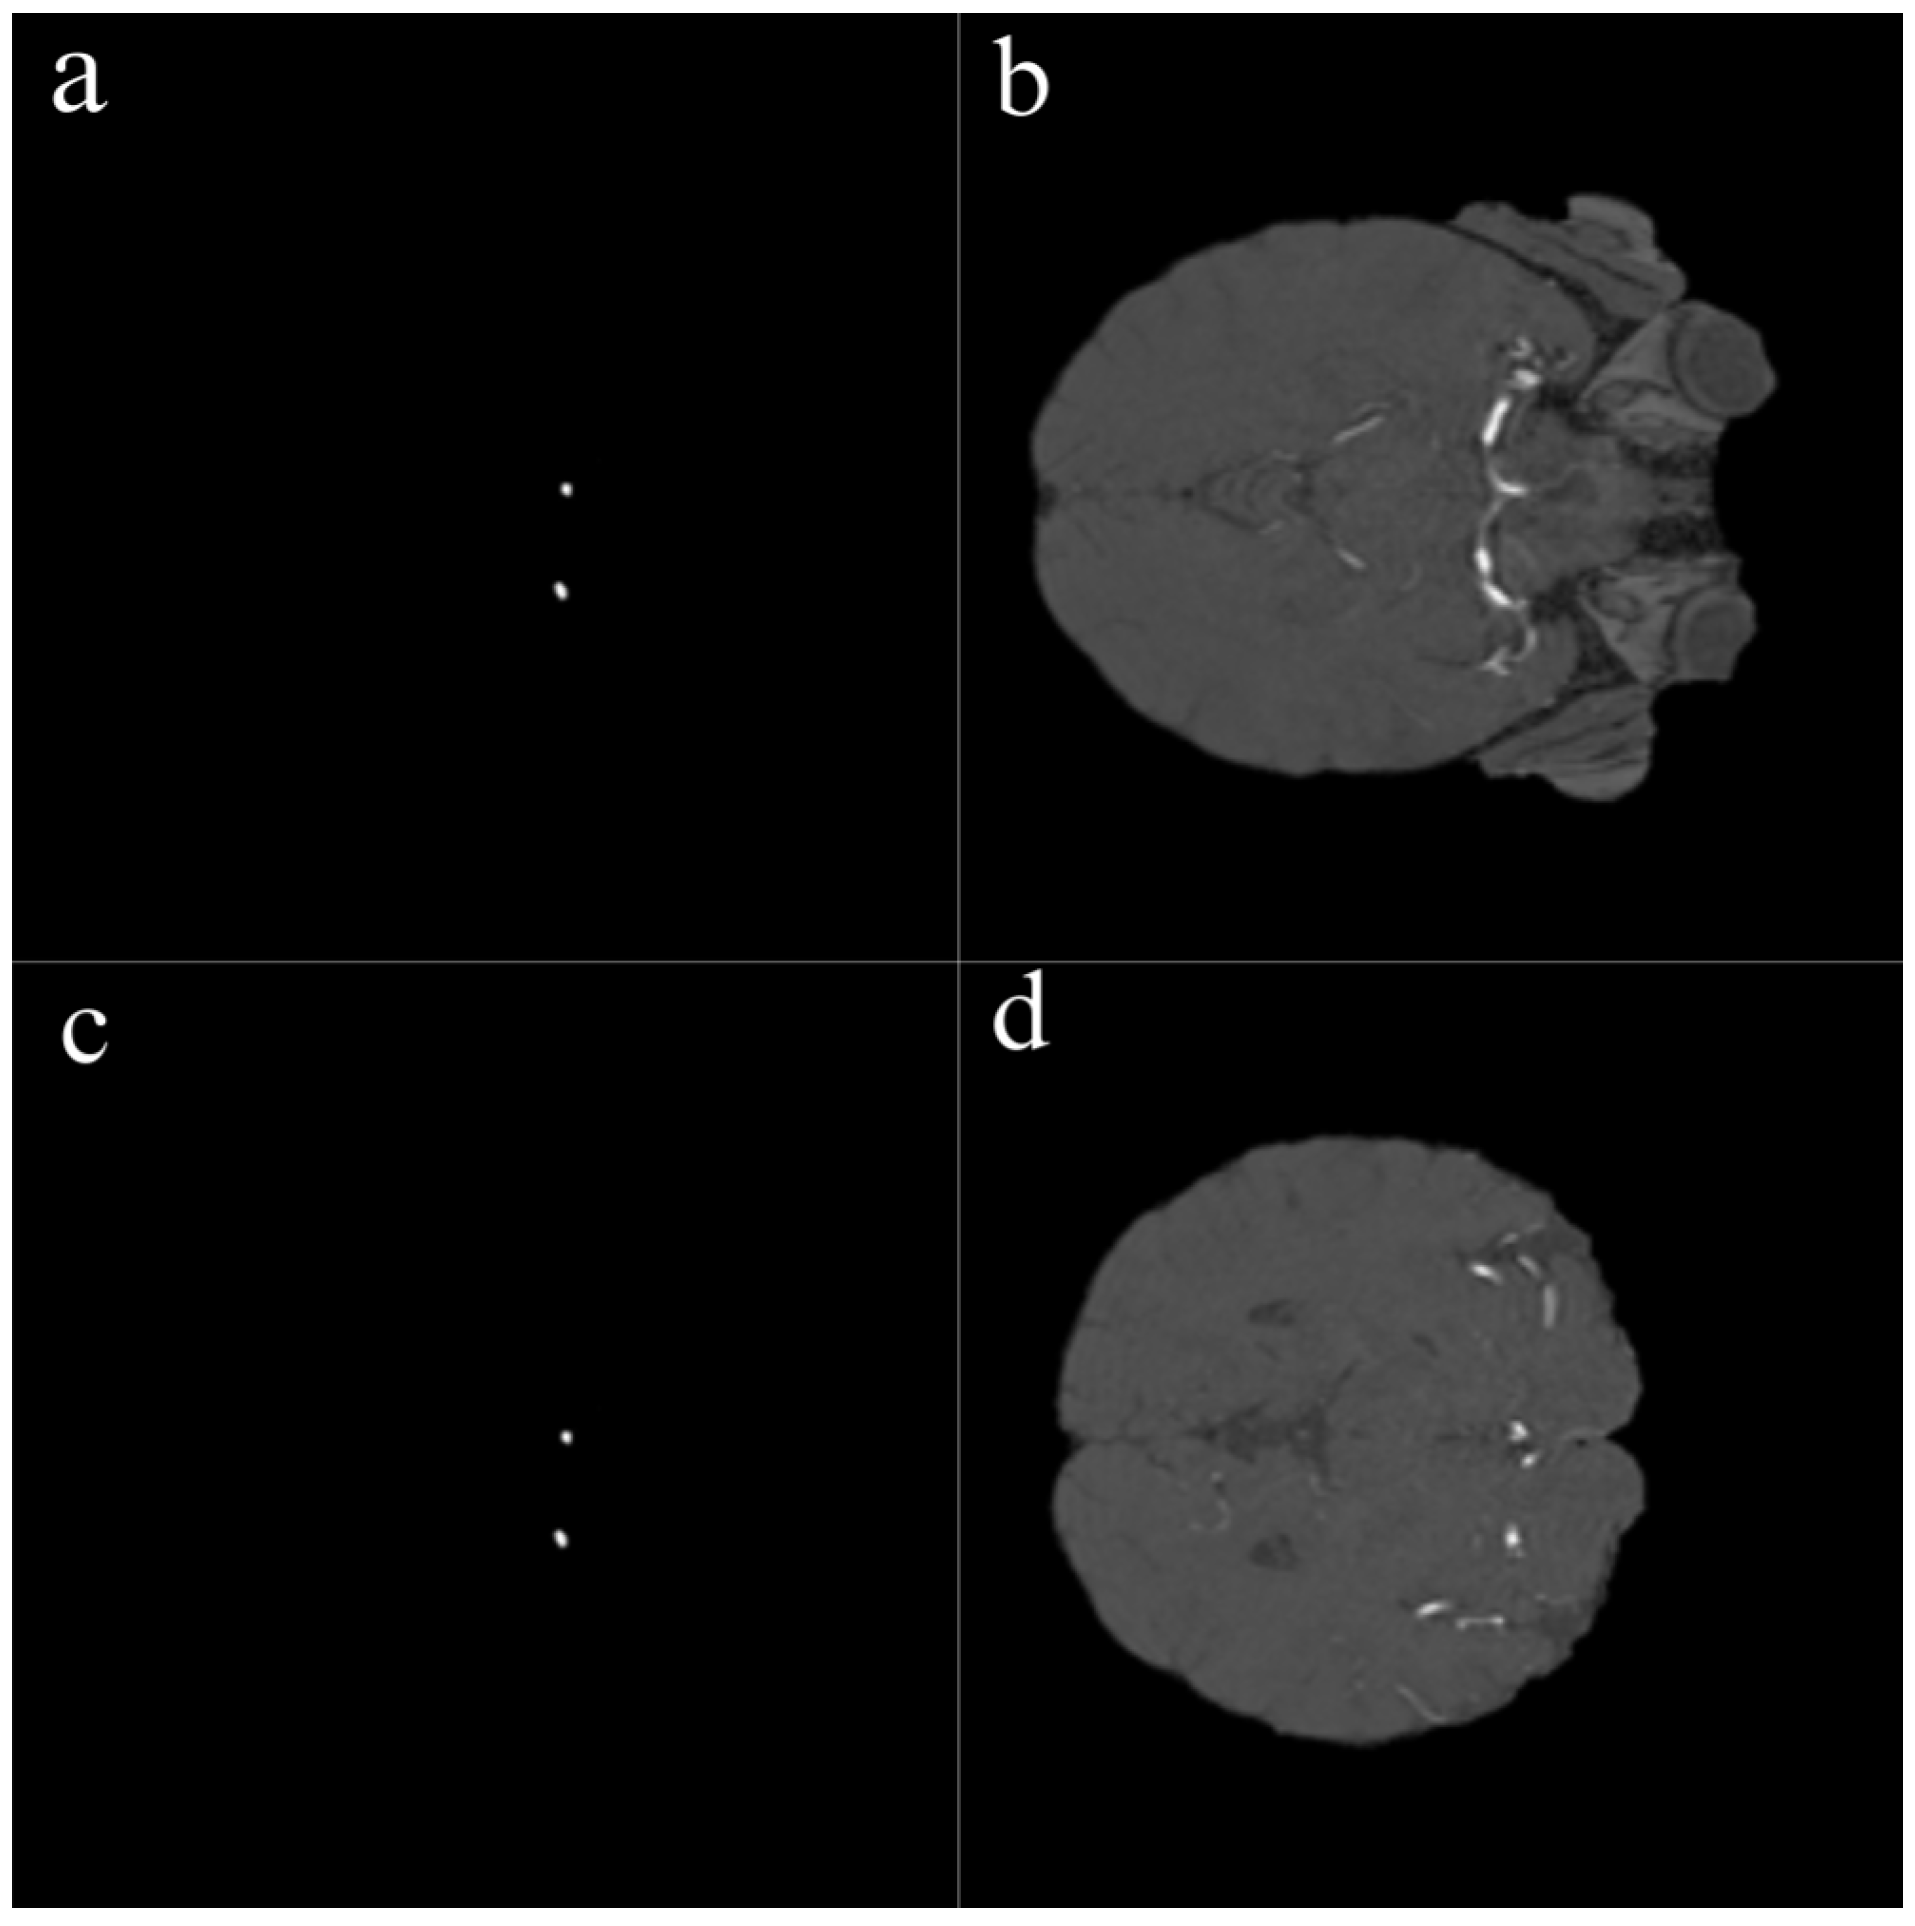

Figure 2. Sample 2D slices and corresponding aneurysm masks derived from TOF-MRA volumes. Left (a,c): Binary segmentation masks showing aneurysm regions in white. Right (b,d): Original TOF-MRA slices corresponding to each mask. Each 3D volume was converted into 2D axial slices, and manual annotations were used to generate ground truth segmentation masks.

In this study, several preprocessing steps were applied to prepare the TOF-MRA images for deep learning. To focus the model on intracranial structures, skull stripping was applied to all TOF-MRA images using FMRIB’s Brain Extraction Tool (BET). By adjusting parameters such as fractional intensity and surface inflation, brain tissue was effectively isolated. Processed images were manually reviewed, and necessary adjustments were made to ensure accurate brain extraction, resulting in a clean dataset suitable for segmentation. The raw data consisted of 3D volumetric brain images stored in NIfTI format (nii/nii.gz). To improve the training performance of the model and standardize the dataset, these volumes were converted into two-dimensional (2D) slices and saved in PNG format. Each image slice was then paired with its corresponding segmentation mask (Figure 2).

One of the most important steps in the preprocessing workflow was the conversion of 3D volumetric TOF-MRA images into two-dimensional slices. Each TOF-MRA sequence was sliced in the axial plane and converted into 2D images, with each slice saved as an individual image file. The same process was applied to the segmentation masks, ensuring that each aneurysmal region was paired with the corresponding 2D image.